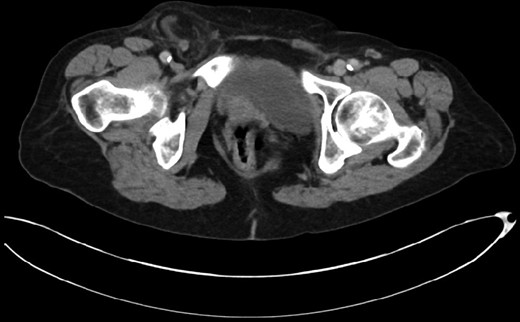

This 82-year-old lady presented with a sudden painful right sided groin swelling not previously noticed. She had no features of obstruction and was opening her bowels and not vomiting. Her medical background included left sided femoral hernia repair in 2005, coronary artery bypass graft and bilateral total knee replacements. On examination her abdomen was soft with the presence of a tender, irreducible swelling in the right groin, inferolateral to the pubic tubercle. She had good bowel sounds and there was stool present in the rectum on PR examination. A full set of blood tests demonstrated no abnormality. A CT abdomen and pelvis demonstrated an incarcerated right sided femoral hernia containing an 8 mm long inflamed appendix with a small amount of localized free fluid and inflammation indicative of De Garengeot’s hernia with underlying acute appendicitis (Fig. 1). The hernia sac diameter measured 2 mm on CT scan. She was taken to theatre for an open Lockwood repair of her femoral hernia and an appendicectomy. Following an initial Lockwood incision over the lump, dissection was performed down to the hernia sac also exposing the inguinal ligament (Fig. 2). The tightness of the femoral ring made mobilization of the appendix difficult. By partially incising the inguinal ligament superior to the femoral ring, the appendix was freed, and on inspection showed inflammation particularly towards the tip (Fig. 3). The caecum was then reduced and the inguinal ligament was repaired with non-absorbable suture. The femoral hernia was then repaired with a small funnel of ultrapro mesh. Appendicectomy was then performed in the usual fashion via the Lockwood incision leaving a slightly longer stump than usual (Fig. 4).

Excised appendix specimen with a slightly longer than usual appendix stump.

The patient had an uneventful recovery and was discharged on the second postoperative day. Subsequent histopathology of the appendix specimen demonstrated serosal inflammation throughout the appendix with partial fibrotic obliteration of the appendix lumen. No formal follow-up was organized and to date there have been no complications following surgery.